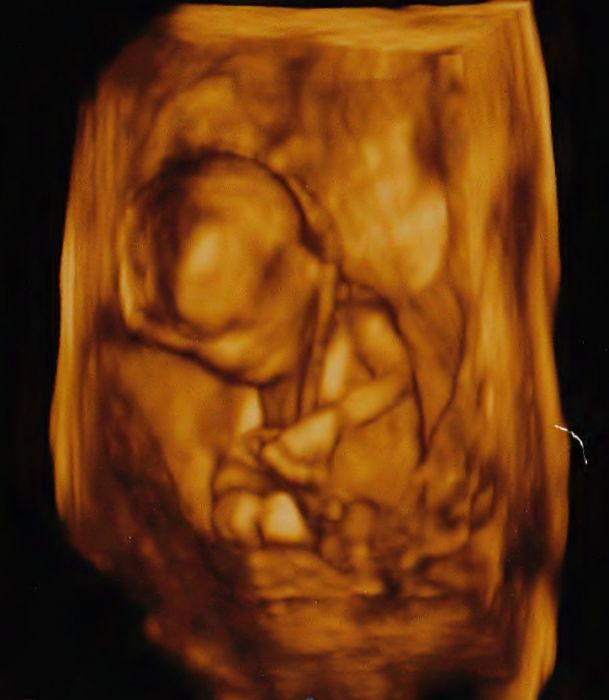

Ahoj Kačko, díky .. no vady srdce jsou prý u 8 plodu z 1000 ...sakra tak to bych nemusela mít to "štěstí" a být zrovna ta z osmi nee... jinak já ted koukam na cele to vyšetřeni znova na DVD... prostě to srdce se nějak zadrhava...jinak je to krásný teda...vidět jak tam ten drobeček skáče a kroutí se a otáčí se prdelkou...nejradši už bych ho měla u sebe venku zdravýho! fotku sem zitra dám. Doktorce jsem volala ted večer - jsem to nevydržela , prý se omlouvá a výsledky krve až zitra že to nestihli dneska.. tak se jeste na telefonu znova zeptam na to srdce

Ahoj Jani, fotecka super, ja mam taky hezky videt, ale jen cernobilou, jak to?? Ja myslela, ze tuto budu mit az v tom 17ctym tydnu.